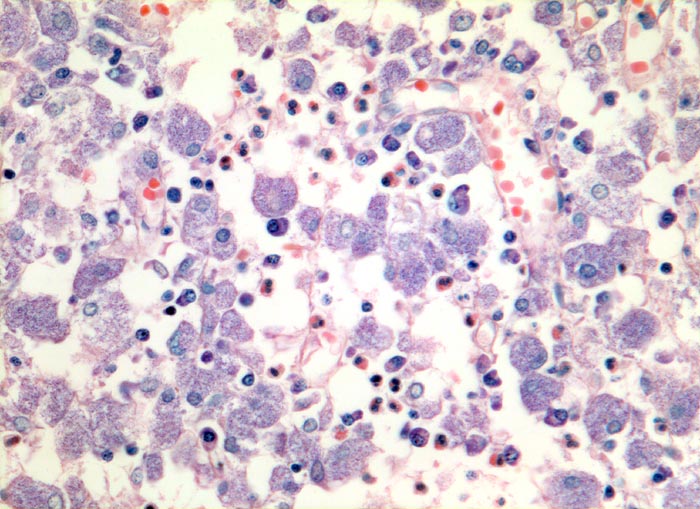

PathoPic – image database / PathoPic ID 3728 - atypische Mykobakteriose (Mycobacterium avium intracellulare)

atypische Mykobakteriose (Mycobacterium avium intracellulare)

Grossleibige histiozytäre Zellen mit fein granuliertem Zytoplasma. Daneben wenig Plasmazellen und Granulozyten.

Ziehl-Neelsen Färbung: die Histiozyten sind voll von säurefesten Stäbchen.

Das Bild der mykobakteriellen Histiozytose wird vor allem durch atypische Mykobakterien verursacht, vereinzelt aber auch durch Mykobakterium tuberculosis.